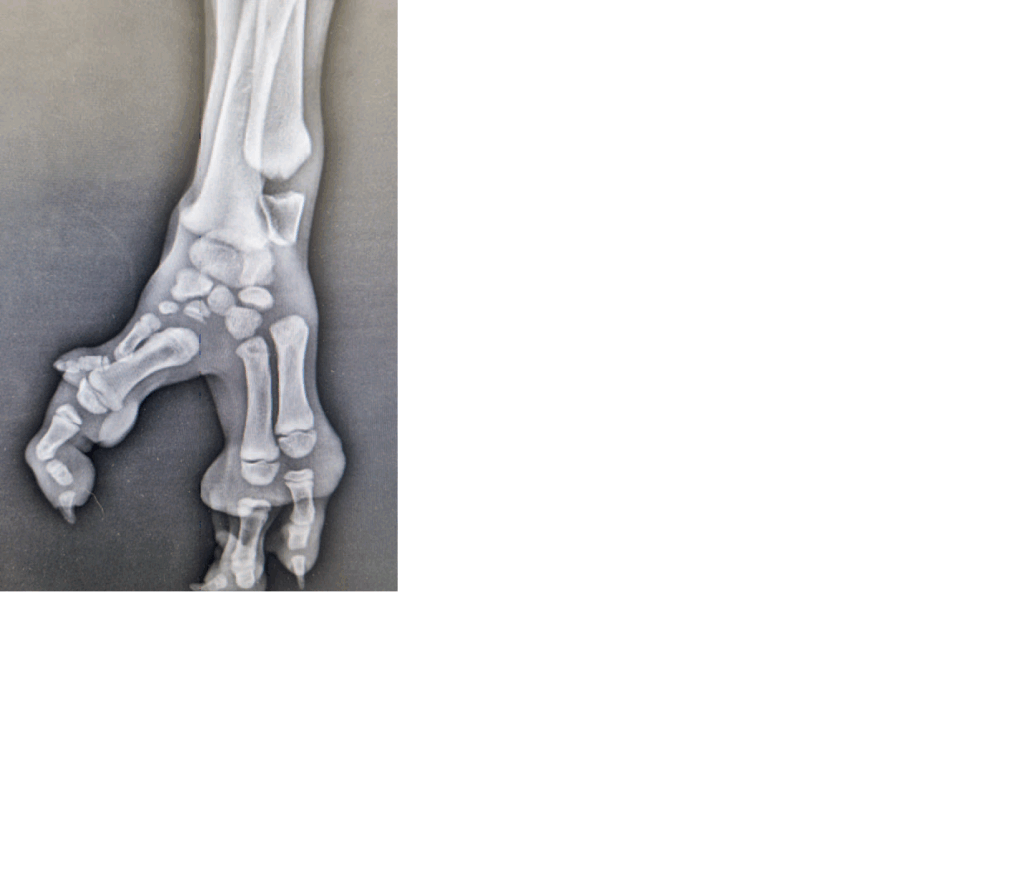

Článek se věnuje chirurgickému řešení vzácné vrozené deformity končetin u psů – ektrodaktylii. Klinické příznaky popsaného případu zahrnovaly rozštěp ruky mezi II. a IV. metakarpální kostí s kulháním na postiženou končetinu. Diagnóza byla potvrzena rentgenologicky, což pomohlo určit rozsah malformace a navrhnout léčbu. Chirurgická léčba nejčastěji spočívá ve vytvoření rigidní fixace pomocí osteosynthetických implantátů. V této publikaci je představen méně používaný způsob fixace metakarpálních kostí pomocí nylonové sutury a fúzní podoplastiky. V popisovaném případu došlo k výbornému zhojení s nízkou pooperační morbiditou a plnou funkčností končetiny.

This study deals with the surgical solution for a rare congenital limb deformity in dogs – ectrodactyly. The clinical symptoms of the described case report included a cleft between the II and IV metacarpal bones with lameness in the affected limb. The diagnosis was confirmed by X-ray, which helped to determine the extent of the malformation and propose treatment. Surgical treatment most often consists of creating rigid fixation using osteosynthetic implants. This publication presents a less commonly used method of fixing metacarpal bones using nylon sutures and fusion podoplasty. In the case described, excellent healing was achieved with low postoperative morbidity and full limb function.*